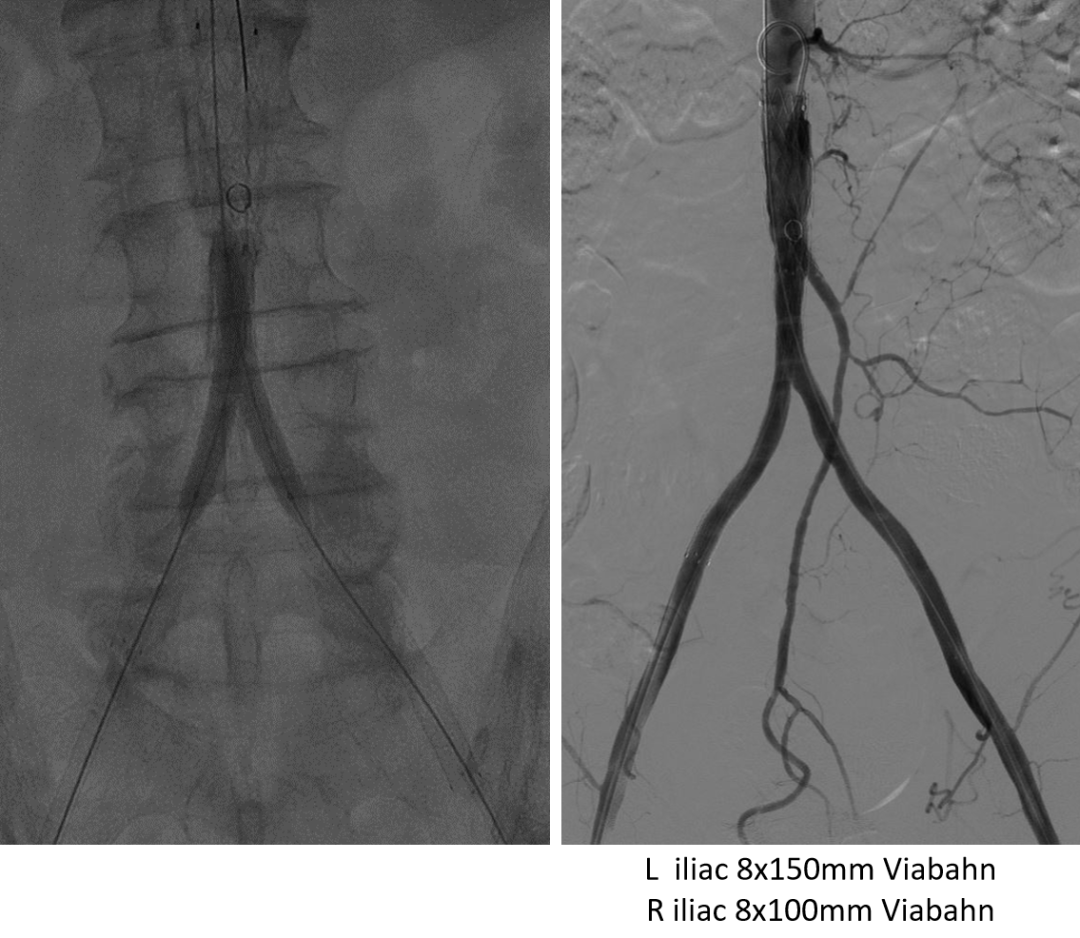

左侧肱动脉入路,主髂动脉造影

双侧股动脉切开,经股动脉7F Fogarty导管取栓

术后结果:ABI改善,症状缓解,无围术期并发症